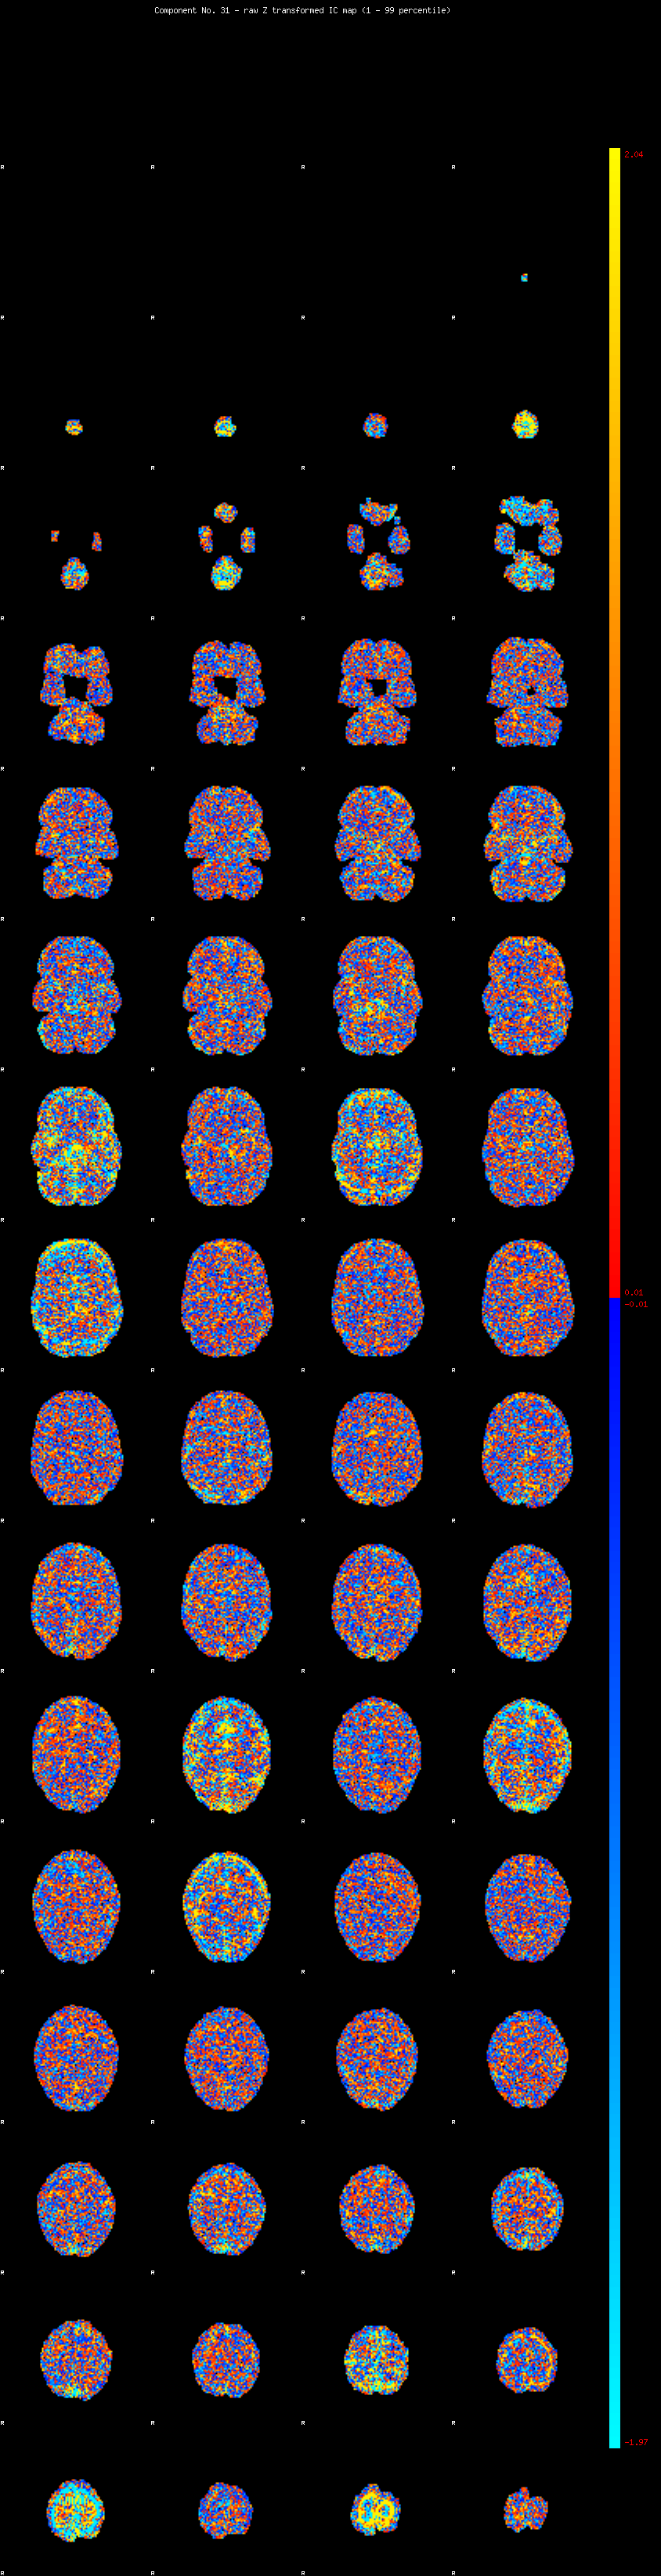

IC_31 Mixture Model fit

Means : -0.000000 3.097452 -2.768098

Vars : 1.000000 4.419120 3.089353

Prop. : 0.939862 0.031676 0.028462